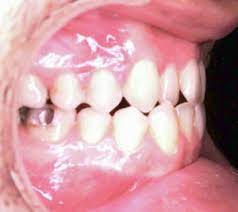

Mal occlusione 1° classe

Agli inizi del secolo scorso, il dott. Edward Angle (in figura) studiò i rapporti che intercorrono fra le arcate, osservate in proiezione laterale (di profilo), quando i denti si trovano in contatto occlusale: basandosi sulle posizioni relative dei primi molari permanenti superiori ed inferiori, Angle individuò tre principali modelli di occlusione, delle quali una (I classe molare) può essere considerata normale, mentre le altre due (II classe e III classe molare) descrivono rapporti non corretti (in visione laterale) fra mascellare superiore e mandibola.

Nelle prime classi, la cuspide mesiale vestibolare (quella verso la parte anteriore della bocca) del primo molare superiore si articola con il solco vestibolare del primo molare inferiore. In pratica, il primo molare superiore si trova più indietro di circa metà dente rispetto al primo molare inferiore.

Un rapporto molare di prima classe non comporta necessariamente un’occlusione ideale: fattori quali le dimensioni dei denti rispetto alla lunghezza delle basi ossee, malposizioni o anomalie dentarie, contrazioni trasversali di una od entrambe le arcate, ecc., possono porre le basi di una malocclusione anche in presenza di un rapporto molare ideale.

Possiamo affermare che le malocclusioni di prima classe sono generalmente più facili da affrontare rispetto a quelle di seconda e terza classe in quanto non prevedono di norma spostamenti in senso mesio–distale (cioè verso destra o verso sinistra se si osserva la bocca in visione laterale, come nelle foto sopra) dei molari superiori nè estrazioni di premolari o altri denti. Può essere comunque necessario ridurre le dimensioni mesio–distali di elementi particolarmente grandi mediante riduzione interprossimale (IPR ostripping) o espandere il diametro delle arcate per risolvere l’affollamento.